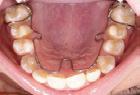

Their technical skills are equally vital. From preparing and sterilizing instruments to taking impressions, digital scans, and radiographs, clinical assistants help ensure procedures are accurate and efficient. Their attention to detail supports the dentist in delivering everything from preventive cleanings and fillings to surgical procedures and orthodontic care. When every second counts and precision matters, a trained assistant is indispensable.

Dr. Brown’s practice focuses on TMJ, sleep apnea and orthodontics. This allows Dr. Brown and his team to provide individualized, focused care for patients dealing with these specific issues. Every day, his practice helps patients of all ages with facial development, sleep issues, chronic headaches, migraines, neck pain, movement disorders, and much more. His training also includes multiple disciplines involving the cranial bones in the skull, and the discs in the jaw joints. Through treatment, Dr. Brown is able to reduce these symptoms, align cranial bones, avoid extractions, and greatly reduce the need for traditional braces. His expertise allows him to identify issues early on which promotes proper facial development using dental appliances. If there is an internal imbalance, whether an adult or child, the body does not develop or function properly. When the cranial bones are lined up correctly, patients are able to function, sleep and generally live better.